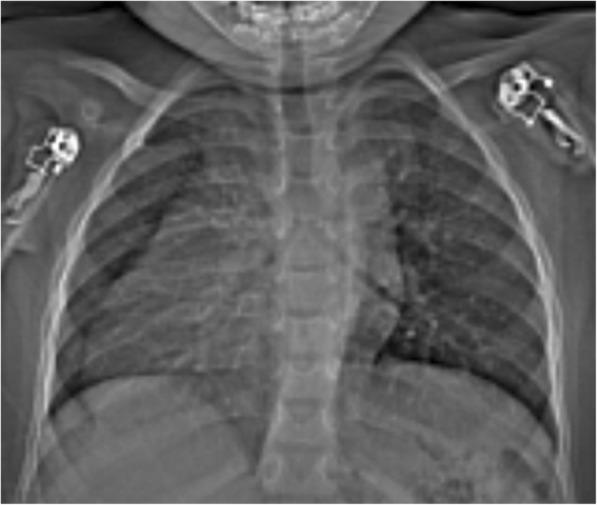

We report a case of a 31- month-old infant black girl in Tanzania who presented with an on-and-off history of difficulty in breathing, easy fatigability, facial and lower-limb swelling, recurrent respiratory tract infections, and failure to thrive.

我们报告了一名来自坦桑尼亚的31个月大黑人女婴的病例,该患儿有断断续续的呼吸困难、易疲劳、面部和下肢肿胀、反复呼吸道感染以及发育不良的病史。